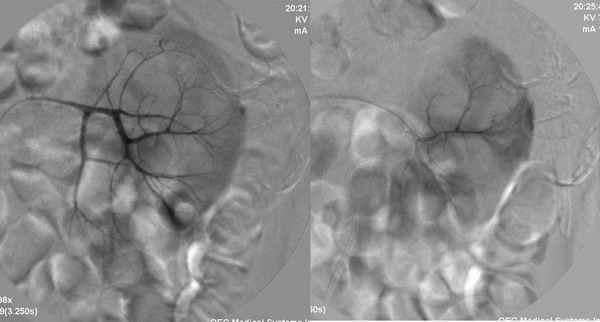

男性,45岁,因左输尿管与肾盂结合部结石住院治疗,经皮肾镜治疗失败后,改做开放手术.手术后3天出现血尿,5天保守治疗仍不能止血,申请肾动脉dsa,见下图片,发帖目的在于请各位分析判断出血部位.

介入治疗过程:

病史已说明肾盂和输尿管交界处结石,穿刺时首先经过包膜--肾实质--肾盂,这样就会有一潜在的通道,包膜下的出血可以延着通道渗入至肾盂、输尿管,所以就有血尿了。